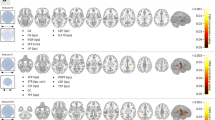

The following descriptions of the tracts are based on a virtual dissection derived from averaged orientation distribution functions (CSD ODFs) from 24 healthy subjects (Figs. 2–6). To probe the individual level results, the same dissections were also performed on the individual level data. The individualized dissections were found to be generally consistent with the average dissection (see Fig. 7 for a representative sample or the online material for the full dataset).

Representation of the identified occipital intralobar tracts in five of the 24 subjects used in this study. The same methodology and regions of interest (ROIs) used to isolate the tracts in the group averaged tractography data. The ROIs were wrapped to native subject spaces. This generates tractography findings that support the presence of the tracts in distinct individuals and depict the subject specific trajectory of the intralobar tracts. VOF vertical occipital fasciculus (green), SRF sledge runner fasciculus (yellow), SPC stratum proprium cunei (magenta), SC stratum calcarinum (red), TFV putative transverse fasciculus of the lingual lobule of Vialet (blue).